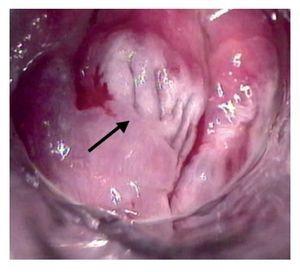

La anoscopia de alta resolución se realizó mediante la siguiente técnica: previa firma del consentimiento informado y con paciente en posición proctológica, se realizó tacto rectal para dilatación del ano, se introdujo anoscopio y se revisó el conducto anal en búsqueda de lesiones macroscópicas. Se aplicó ácido acético a 3% con un hisopo y se retiró el anoscopio. El hisopo se dejó en contacto con las paredes el conducto anal por un minuto y se retiró. Se introdujo nuevamente el anoscopio y se realizó la observación del conducto anal con microscopio de alta resolución. En los casos que se consideró necesario, a criterio del colposcopista, se utilizó la prueba de Schiling para detectar las lesiones sospechosas. Esta prueba consiste en aplicar una solución yodoyodurada de lugol a 1% o 2%, con el objeto de obtener imágenes yodo negativas (que no fijan el lugol), yodo positivas o yodo débiles (que fijan el lugol). El fundamento es que únicamente los tejidos maduros, provistos de glucógeno fijan el yodo, razón por la que el epitelio maligno o atípico es yodo negativo (Figuras 1-3). En las lesiones que resultaron dudosas para VPH o NIA se tomaron 1 o 2 biopsias de la lesión sospechosa. Previo al procedimiento, los pacientes acudieron con preparación intestinal a base de enemas de fosfato. No se administró profilaxis antibiótica y el procedimiento se realizó sin anestesia.

Figura 2. Anoscopia de alta resolución muestra un patrón aceto-blanca difuso con puntilleo vascular y ulceración. Lesión sospechosa de neoplasia intraepitelial anal de bajo grado, en la cual se utilizó filtro para resaltar la lesión